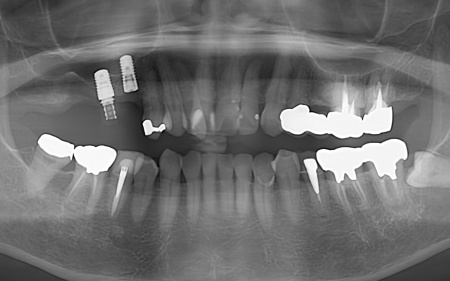

拝見したところ、右上の歯には、欠損部位前後の歯を土台として橋を渡すように連結した被せ物「ブリッジ」が装着されていました。

しかし、土台となっている手前の歯(第2小臼歯)は歯根が割れており、同じく土台となっている奥の歯(第2大臼歯)は歯根の先に膿の袋ができる「根尖病巣(こんせんびょうそう)」が認められます。

また抜歯後に歯を補う方法のひとつにインプラント治療がありますが、患者様の場合は治療に必要な骨量が確保できないため難しいとされ、取り外し式の入れ歯になるとのことでした。

抜歯と根管治療を行ったあとは、欠損部を補うために、2本のインプラントを埋入する方法を提案しました。

インプラントを埋入するために必要な骨量が足りない場合は、鼻の空洞(上顎洞)の粘膜を少しずつ押し上げて骨を増やす「ソケットリフト」を併用することもお伝えしています。

その間、右上奥歯2本が欠損したままでは噛み合わせが崩れるリスクがあったため、早期にすでに欠損していた右上奥歯(第1大臼歯)部位にのみ、インプラントの埋入を行いました。

約4ヶ月後、歯槽骨の再生が確認できたため、もう1本のインプラントを埋入しました。

右上奥歯は2本とも骨の高さが不足していたので、治療の際はソケットリフトを併用しています。